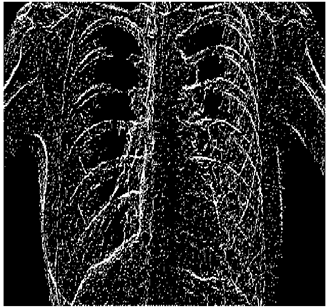

Table 12. Edge-detected image of “X-ray 3” after binarization for different noises.

NoiseCannyStandardSmooth

No noise Mathematics 10 02421 i114 Mathematics 10 02421 i115 Mathematics 10 02421 i116

G(0.001) Mathematics 10 02421 i117 Mathematics 10 02421 i118 Mathematics 10 02421 i119

G(0.002) Mathematics 10 02421 i120 Mathematics 10 02421 i121 Mathematics 10 02421 i122

G(0.003) Mathematics 10 02421 i123 Mathematics 10 02421 i124 Mathematics 10 02421 i125

I(0.25%) Mathematics 10 02421 i126 Mathematics 10 02421 i127 Mathematics 10 02421 i128

I(0.5%) Mathematics 10 02421 i129 Mathematics 10 02421 i130 Mathematics 10 02421 i131

I(1%) Mathematics 10 02421 i132 Mathematics 10 02421 i133 Mathematics 10 02421 i134

For Table 11, Table 12 and Table 13, the same points of Table 10 can be made. Therefore, for the sake of brevity, the points are not mentioned.